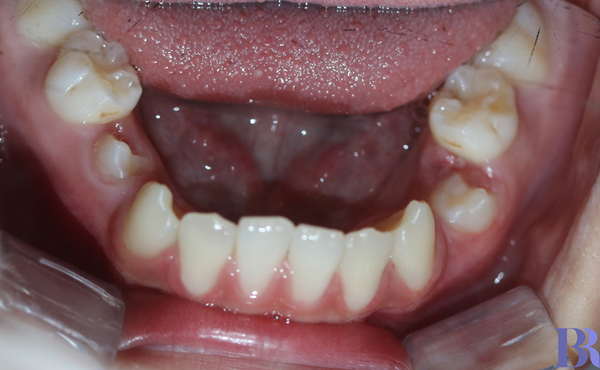

아랫니가 심하게 거꾸로 물림(반대교합)

교정 전 오른쪽 모습

반대교합 양상이 심한 것을

알 수 있습니다.

과연 교정으로만 해결할 수

있을까 싶을 정도입니다.